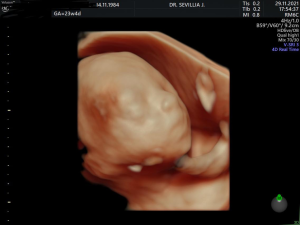

ד"ר ג'קי סביליה

מומחה ביילוד גניקולוגיה ואולטרהסאונד , סקירת מערכות מוקדמת ומאוחרת בטכנולוגיית תלת מימד וב D4

גלריית תמונות